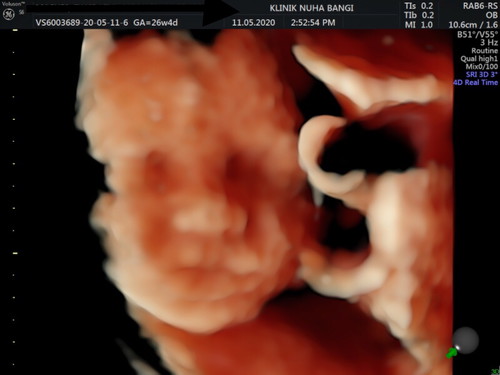

first time saya buat scan detail n 4d kt swasta, alhamdulillah bby sihat doktor sah kan it baby girl ? patut la pun saya suka sngat mkan benda2 manis, lagi2 klau dapat aiskrim sdap nyaa laa ?